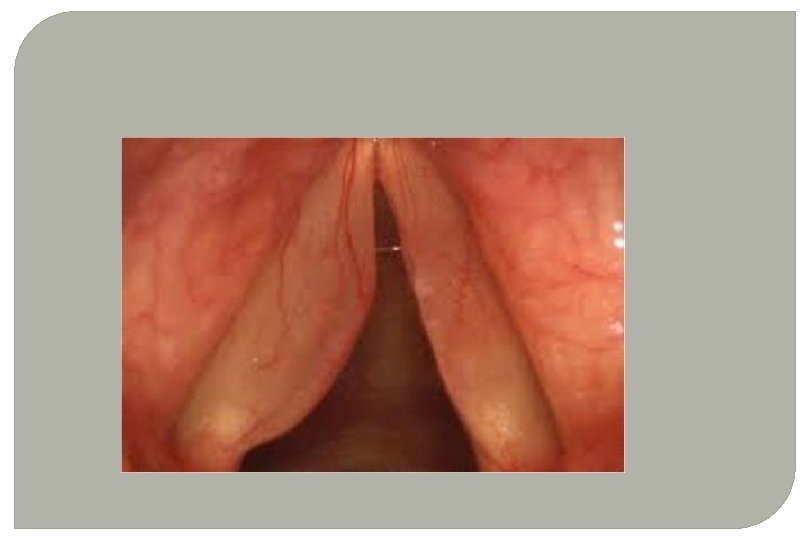

POLYPOID DEGENERATION OF VOCAL CORDS (REINKE'S OEDEMA) • Bilateral symmetrical swelling of membranous part of the VCs. • Middle-aged men and women • Oedema of the subepithelial space (Reinke’s space) of the VCs • Chronic irritation of VCs due to misuse of voice, heavy smoking, chronic sinusitis and laryngopharyngeal reflex

Clinical Features • Hoarseness • False cords for voice production - low pitched and rough voice • VCs - fusiform swellings with pale translucent look. • Ventricular bands may appear hyperaemic and hypertrophic